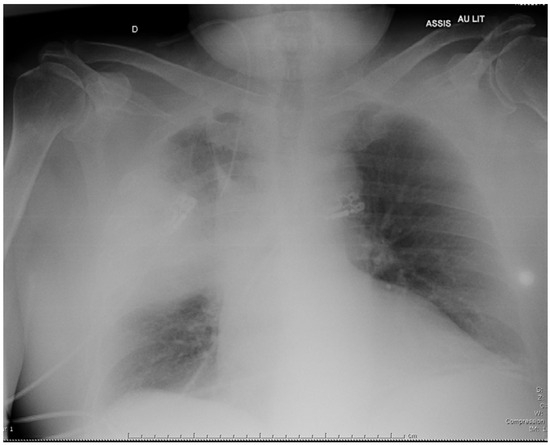

A 69-year-old man presented in November 2018 with a 3-day history of cough and fever. He reported significant tobacco consumption, type 2 diabetes, obstructive sleep apnea (OSA) and rheumatoid arthritis (RA) treated with successive tumor necrosis factor-alpha inhibitors since 2004. His immunosuppressive therapy had been strengthened with high-dose corticosteroids in August 2018 because the RA had relapsed, and etanercept had just been replaced by abatacept (an inhibitor of the cytotoxic T lymphocyte-associated antigen-4 receptors) few days prior to admission. The first evaluation revealed: temperature of 37.9 °C, blood pressure of 126/69 mmHg, respiratory rate of 32/min, and oxygen saturation of 95% on 3L/min of O2. He was alert but complained of cough and dyspnea. The chest examination mainly revealed crackles in the right field. Initial lab work showed: hemoglobin 12.8 g/dL, WBC count 9,600 /µL, platelet count 178,000 /µL, creatinine level 22.3 mg/L, C-reactive protein 514 mg/L, and procalcitonin 4.9 ng/mL. On room air arterial blood gas showed pH of 7.50, O2 pressure of 53 mmHg, and CO2 pressure of 34 mmHg. Chest X-ray demonstrated alveolar infiltrates in the middle part of the right lung (Figure 1). The patient received intravenous (i.v.) cefotaxime, 2 g every 8 h, plus i.v. levofloxacin, 500 mg daily, as empirical therapy, then was admitted to the intensive care unit because he required non-invasive ventilation.

Figure 1. Chest X-ray on admission showing a right consolidation in the right lung.